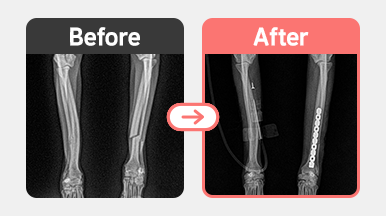

[요척골 골절 수술] 푸들 / 4살 / 좌측 전지 골절

품종 : 푸들

나이 : 4살

체중 : 4.1kg

진단명 : 전지 좌측 요척골 골절

치료내용 : 좌측 요척골 골절 수술 (내고정술) 진행

4살 푸들이 낙상 후 왼쪽 앞다리를 디디지 못한다는 증상으로 내원하였습니다.

신체 촉진 및 방사선 촬영 결과,

좌측 전지(앞다리)의 요척골(radius & ulna) 골절이 확인되었습니다.

골절된 부위는 내고정술을 통해 정복 및 고정하였으며,

수술 후 현재는 통증 감소 및 점진적인 보행 회복이 이루어지고 있습니다.

푸들 4살 좌측 전지 요척골 골절 수술 사진